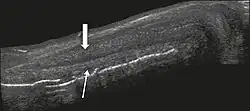

Figure 4 A: Ultrasound of the penis, right lateral view. Longitudinal section showing rupture of the tunica albuginea with an adjacent 1.92 cm hematoma (between calipers), due to trauma.[1]